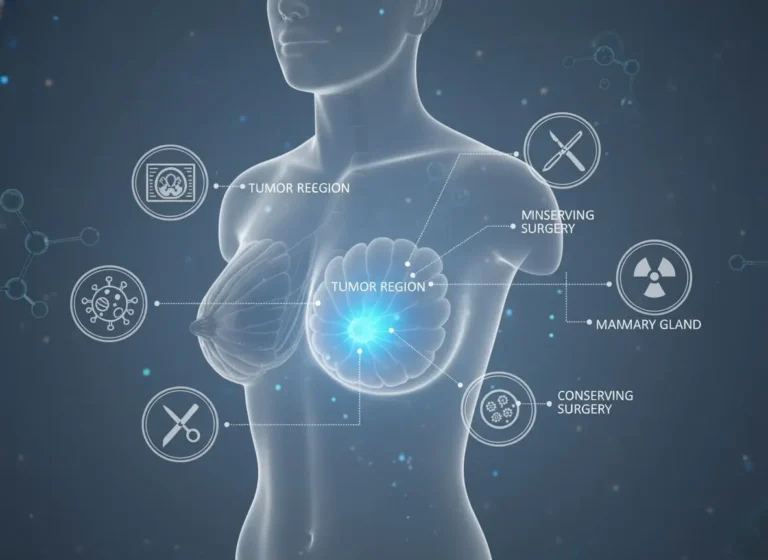

Empowering Healing: Advanced Breast Cancer Surgery in Borivali Hospital

From the first word, insight begins to illuminate the way; discovery flows naturally into purpose Breast cancer remains one of the most…

From the first word, insight begins to illuminate the way; discovery flows naturally into purpose Breast cancer remains one of the most…